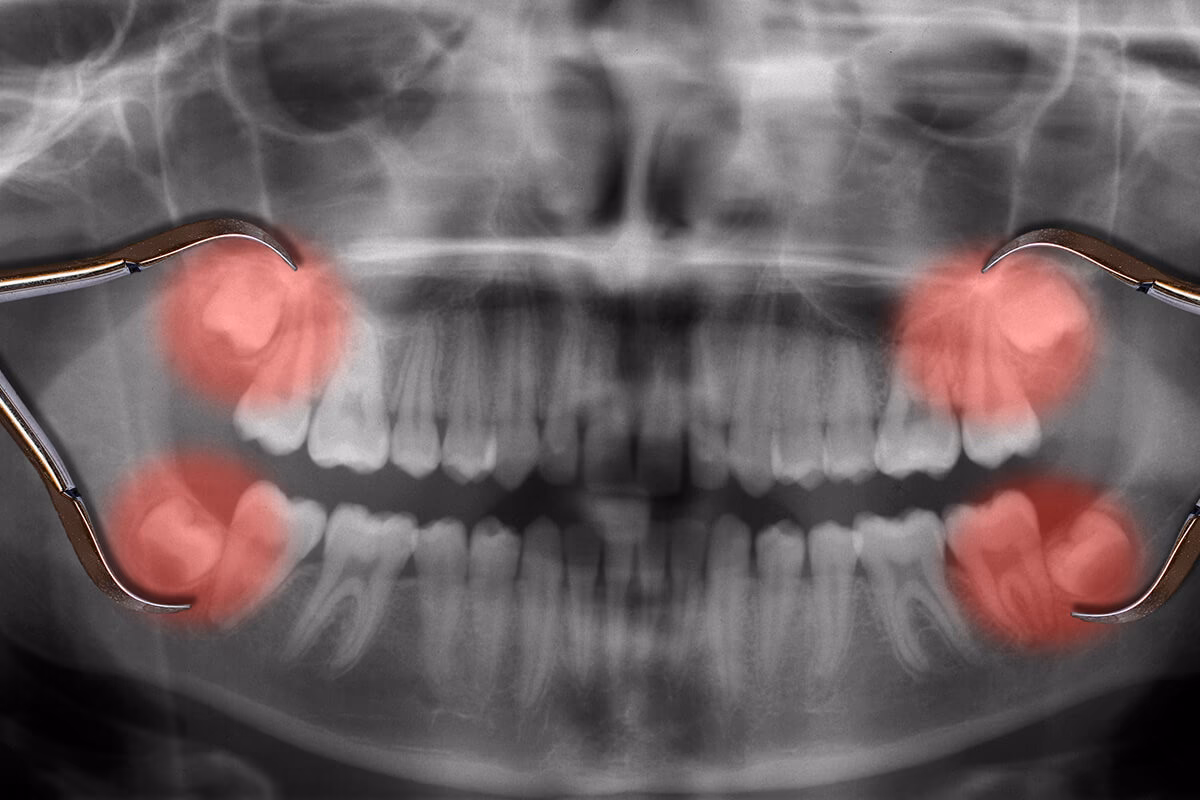

- Indkapslede visdomstænder: Dette er den hyppigste årsag. En indkapslet visdomstand betyder, at den ikke har plads nok til at bryde helt eller delvist igennem tandkødet. Den kan vokse i en forkert vinkel, mod den næste tand, mod bagsiden af munden, eller den kan forblive fanget i kæbeknoglen. Dette kan forårsage smerte og skade på nabotænderne.

Under den indledende konsultation vil kirurgen tage røntgenbilleder for at vurdere visdomstændernes position, form og forhold til nerver og kæbeknogle. I vil diskutere, hvilken type bedøvelse der er bedst for dig. Mulighederne inkluderer: